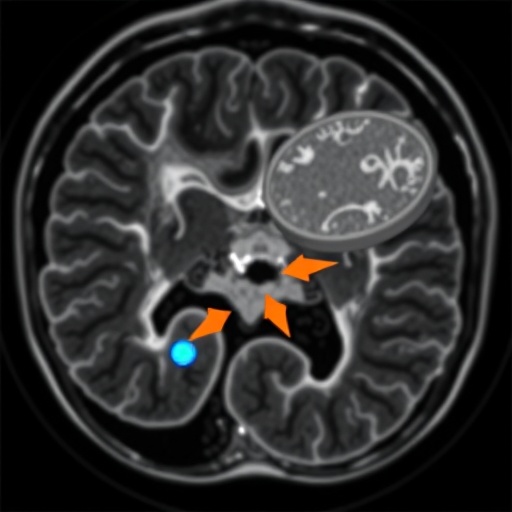

Crohn’s disease is notorious for its unpredictable nature, often leading to strictures, which are narrowing of the bowel that can result in painful digestive complications. These strictures can complicate treatment regimens and significantly impact a patient’s quality of life. The current study aims to address this challenge by employing MRI techniques to quantify ileal motility. This approach could serve as a non-invasive method to predict how well strictures in patients will respond to biologic therapies, which are medications designed to modulate the immune response and alleviate inflammation.

The research involved a cohort of patients diagnosed with Crohn’s disease, each experiencing varying degrees of ileal stricture. Utilizing advanced MRI technology, the team successfully quantified the peristaltic movements of the ileum – the final section of the small intestine. This detailed analysis provided insight into the motility patterns of the affected areas, allowing the researchers to correlate specific motility characteristics with treatment responses observed post-therapy. The outcome was not only quantitatively impressive but also indicative of a new era in personalized medicine for Crohn’s patients.

As the field evolves, the relevance of early intervention cannot be overstated. Identifying stricture development and the likely response to biologic therapy before symptoms escalate into emergencies can dramatically enhance patient outcomes. By enabling clinicians to act preemptively, the MRI-based motility assessment not only gives patients hope but also empowers healthcare providers with the knowledge necessary for proactive care, ultimately striving to transform Crohn’s disease from a chronic struggle into a manageable condition.